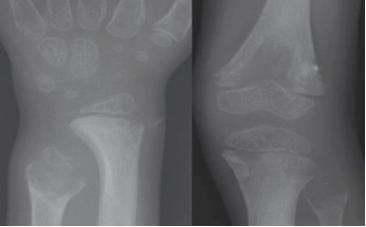

Hipofosfatasia Pediátrica: Es la forma clínica que se manifiesta desde los 6 meses hasta los 18 años de edad, sus manifestaciones son ampliamente variables en presentación y en severidad, los pacientes pueden presentar pérdida prematura de los dientes, usualmente indolora y con raíz intacta; las formas con sintomatología clínica más severa presentan dolor óseo significativo, debilidad muscular y dificultad para hacer tareas de la vida diaria como jugar o subir escaleras, impactando significativamente la calidad de vida de los niños y adolescentes; dentro de los hallazgos radiológicos característicos se encuentra las “lenguas de radiolucencia” en los huesos largos que se proyectan de las placas de crecimiento a las metáfisis (figura 2), otros hallazgos incluyen fisis irregulares. Los adolescentes con HPP pueden tener talla baja y reportar fracturas metatarsianas de difícil consolidación (4,5,6).

Figura 2. En el gráfico se evidencian las lenguas de radiolucencia en todas las metáfisis. Der: La irregularidad metafisaria es especialmente prominente en la cabeza del peroné - femur distal - tibia proximal. Izq: La irregularidad metafisaria es especialmente prominente en el cúbito distal.